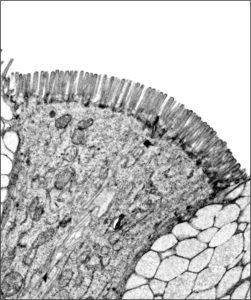

Electron micrograph showing Microvilli on the top side of intestinal cells in humans and C. elegans.

The top side of intestinal cells is decorated with numerous highly organized, finger-like projections called microvilli. These specialized structures form the brush border, which increases the absorptive surface area of the cell manyfold and is indispensable for nutrient uptake and organismal survival. Brush border atrophy can be caused by genetic diseases, pathogens, toxins, and often results in complications such as chronic diarrhea, which can prove fatal. Currently, our understanding of brush border atrophy is limited, and only preventive measures are available to mitigate the symptoms. Through this project, we are making an attempt towards understanding this process and developing regenerative approach in the hope of providing better alternatives to the treatments currently employed.